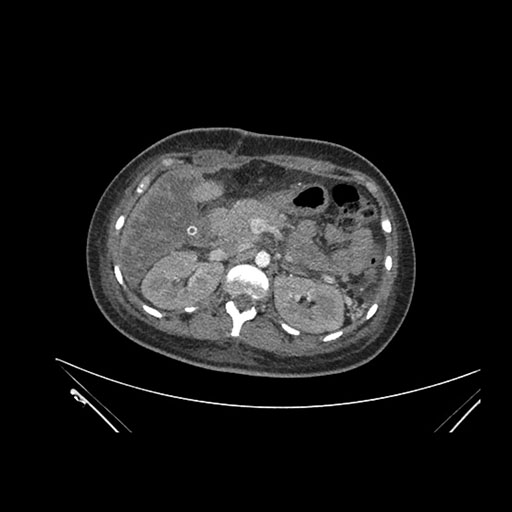

Imaging Analysis

Look through the patient's CT scan to identify any areas of concern for the necessary procedure.

Coronal Arterial